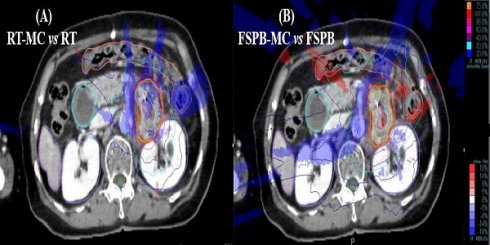

Accuracy analysis of different dose calculation algorithms for locally advanced pancreatic cancer stereotactic body radiotherapy Yongchun Song, Xuyao Yu, Yuwen Wang, Yang Dong, Zhiyong Yuan J. Cancer 2023; 14(14): 2694-2699. doi:10.7150/jca.87596 Full text PDF PubMed PMC